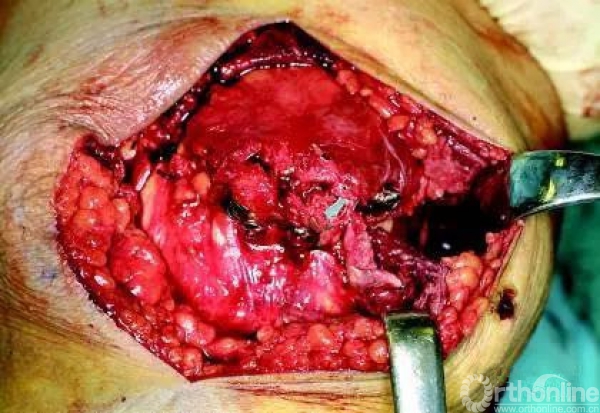

采用纵向切口,术中探查,下极十分粉碎无法修复,采用两枚铆钉置入中断骨折断端

将缝线沿髌骨下极两侧腱膜出缝出,然后缝两个loop后互相打结